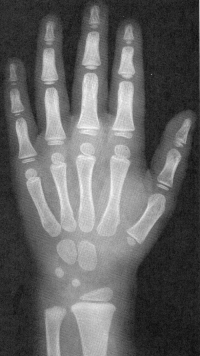

Sexo Masculino

6 meses

9 meses